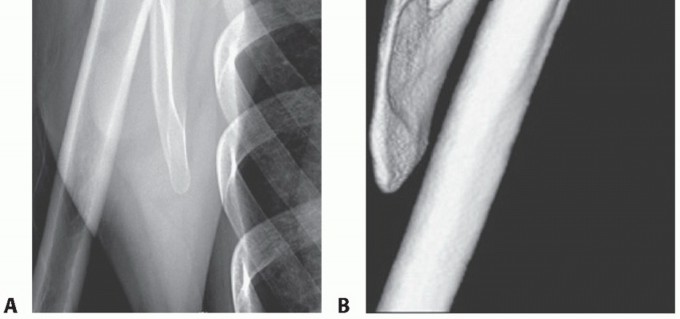

Magnetic Resonance Imaging (MRI), particularly T2-weighted and STIR sequences, is indispensable for evaluating soft tissue pathology. MRI effectively demonstrates bursal fluid, synovial hypertrophy, fibrotic masses, and soft tissue tumors (e.g., elastofibroma dorsi) that may be responsible for the mechanical snapping.

Computed Tomography (CT) with 3D volumetric reconstruction is the gold standard for evaluating the osseous morphology of the superomedial angle. It precisely delineates the anterior curvature of the scapula, identifies osteochondromas, and assesses thoracic cage congruency.